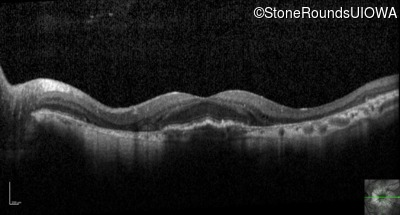

Optical Coherence Tomography - Right - 20/40 -2

Exemplar / OCT Stack